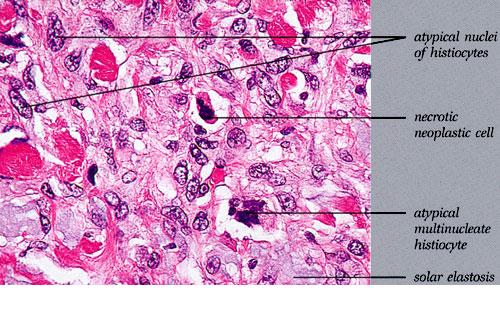

malignant-fibrous-histiocytoma